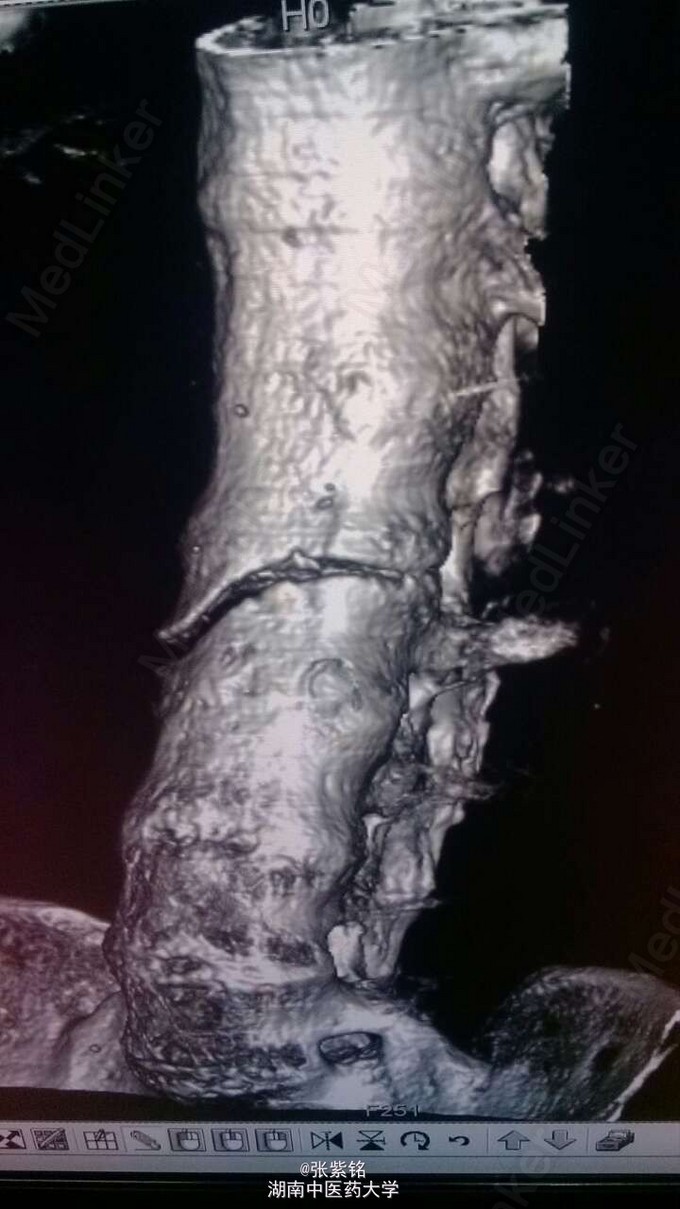

查体见:左额部可见约2cm*2cm皮下血肿,并可见一不规则伤口约2cm,伴活动性出血。脊柱驼背畸形,胸椎后凸,头部前伸体态;颈、腰部旋转活动不能,腰部于L3-5椎体棘突处压痛明显,双下肢肌力、肌张力正常。左肩部关节明显肿胀,可扪及空虚感;局部压痛明显,左Dugas征阳性,左肩关节主动上举,外展,后伸,内收活动受限;被动活动患处疼痛加剧,左侧桡动脉搏动可扪及,皮肤感觉正常,左肘、腕及各指间关节血运感觉活动正常。 X线片示:左肩关节脱位,左肱骨外科颈骨折,左肱骨大结节撕脱性骨折。